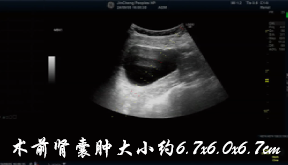

80岁的张奶奶5天前突然发现颈部肿物,还伴着明显胀痛,就诊于我院急诊外科。由于她患有高血压、糖尿病、冠心病等多种基础疾病,外科手术风险较高,医生随即建议转至介入与血管外科。王丽云副主任会诊后明确诊断:甲状腺右侧叶囊肿伴囊内出血,囊肿大小达4.0x3.2x2.6cm。考虑到患者高龄且基础病多,决定采用微创的甲状腺囊肿硬化治疗术,无需开刀、创伤小、恢复快,完美规避了传统手术的风险。